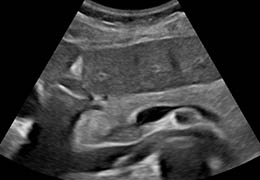

View X-Ray CT & MRI Scans Fast and Easily

FREE and easy to use 3D DICOM Viewer – for surgeons and patient education

Designed for surgeons, Pro Surgical 3D makes it easy to view patient scans quickly. Pro Surgical 3D facilitates the optimal 3D treatment and assessment workflows based on X-ray CT and MRI scans – and best of all, it’s FREE!

Everyone – including surgeons, patients and their loved ones – benefits from being better informed by the wealth of information buried within CT and MRI scans. Pro Surgical 3D gives surgeons more information to develop optimal treatment plans for patients. It also helps patients and their support group better understand their medical condition and proposed treatment options.

Designed mainly for CT and MR DICOM modalities.

Multi-planar slicing.